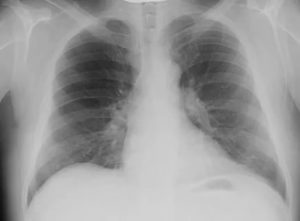

Часто пациенты, которых направляют на обследование, задаются вопросом, покажет ли рентген пневмонию. Да. С помощью такой процедуры на снимке можно увидеть воспаленные участки, оценить состояние легочного рисунка и корней легких.

Расшифровка пневмонии на рентгеновских снимках проводится по четырем признакам: изменение рисунка и корней легкого, затемнения и просветления. Признакам, указывающим на пневмонию, которые можно увидеть на снимках, свидетельствуют такие критерии:

- полное затемнение легочной ткани;

- затемнение некоторых участков или долей легкого (правое легкое состоит из трех долей, левое – из двух);

- затемнение определенного сегмента легкого.

По размеру затемнения (овальные, круглые или кольцевидные) могут быть мелкими (до 3 мм), средними (до 7 мм) и большими (тотальными). Участки поражения могут быть единичными или обширными.

На фото видны признаки пневмонии:

- светлые полости;

- размытые контуры воспалительных очагов;

- затемнения за счёт уплотнений.

Сравнение здоровых и воспаленных легких на рентгенографии Абсцесс лёгких на рентгеновском снимке Абсцесс при левостороннем верхнедолевом воспалении лёгких Очаговая пневмония Крупозная пневмония на рентгене Казеозная пневмония